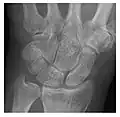

Occult osseous injuries may result from a direct blow to the bone by compressive forces of adjacent bones against one another or by traction forces during an avulsion injury. Lesions in the tibial plateau, hip, ankle, and wrist are often missed. In a tibial plateau fracture, any disruption of the posterior and anterior cortical rims of the plateau should be sought. Impaction of subchondral bone will appear as an increased sclerosis of the subchondral bone (Figure 1). In the hip, posterior acetabular fractures also present subtle radiographic findings. The acetabular lines should then be carefully examined keeping in mind that the posterior rim, which is harder to see on X-rays, is more frequently fractured than the anterior rim (Figure 2). In the wrist, detection of carpal bone fractures is often challenging, with up to 18% of scaphoid fractures radiographically occult. Carpal fractures, especially the scaphoid, are associated with the risk of avascular necrosis. In apparently normal wrist radiographs from symptomatic patients, if there is history of a fall on an outstretched hand with pain in the anatomic snuffbox, suggesting scaphoid injury, the initial examination with posteroanterior, lateral, and pronation oblique views must be complemented by other specific views such as supination oblique and the "scaphoid" view A careful examination of cortices for evidence of discontinuity or offset and cancellous bone for lucency is necessary (Figure 3).[1]

-

a

b

c

Figure 3: A 26-year-old man presenting with wrist pain after being assaulted. (a) Initial anteroposterior radiograph shows a subtle linear lucency within the scaphoid extending to the scaphocapitate articular surface that was overlooked (arrow). (b) Initial "scaphoid" view was negative. (c) Followup anteroposterior radiographs, 12 days later, shows obvious scaphoid fracture (arrows).[1]